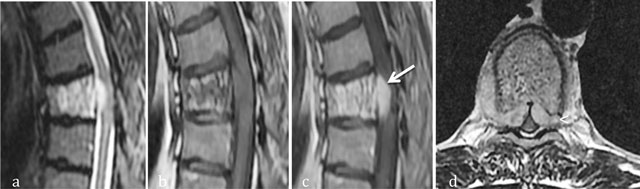

Figure 5

Aggressive hemangioma of T5. Sagittal T2-WI (a), Sagittal T1 WI (b) and sagittal (c) and axial (d) T1-WI after gadolinium contrast administration (c) MR images shows an aggressive hemangioma of T6 with extension into the anterior epidural space (arrow) and soft tissues (arrowhead).